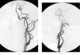

Anomalous left common carotid artery